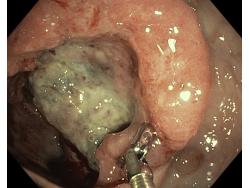

Nowotwory przewodu pokarmowego

Zabiegi endoskopowe